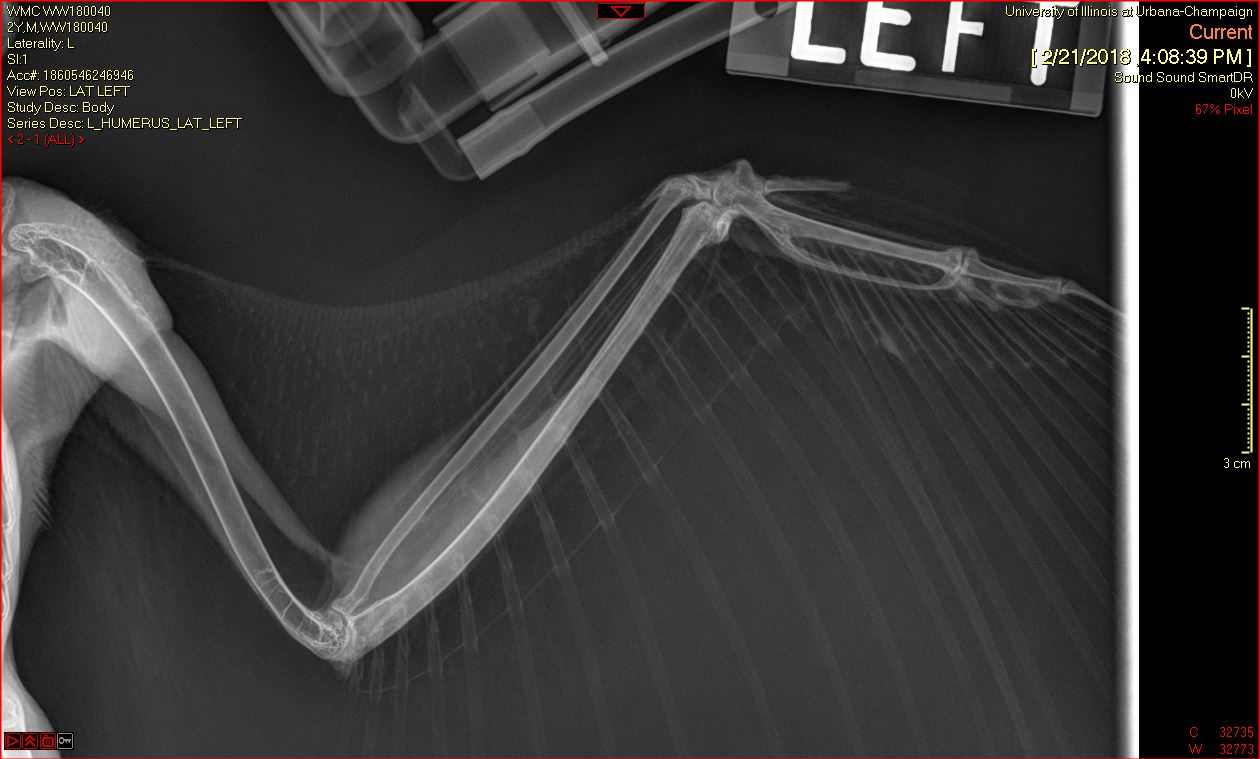

A Barred Owl was transferred to the Wildlife Medical Clinic from a nearby veterinary clinic on February 20th after being hit by a car on February 18th. In their initial exam, the team noticed an open fracture on the middle of the right humerus of the wing. Radiographs (x-rays) showed that the wing had been rotated a complete 360 degrees!

Once the wing was rotated back into normal position, the team had to wait to assess whether the portion distal to the rotation (closer to the wing tip) still had healthy blood supply. Once this was ensured, they determined the owl was a good candidate for surgery to repair the humeral fracture.

The team was happy with the placement of the pins! However, as they continued to monitor the owl, they noticed it squinting its right eye. On further investigation, team leaders determined that the owl could not see out of its right eye and that an injury was causing discomfort. So, the owl underwent surgery again, this time an evisceration procedure to remove the eye.